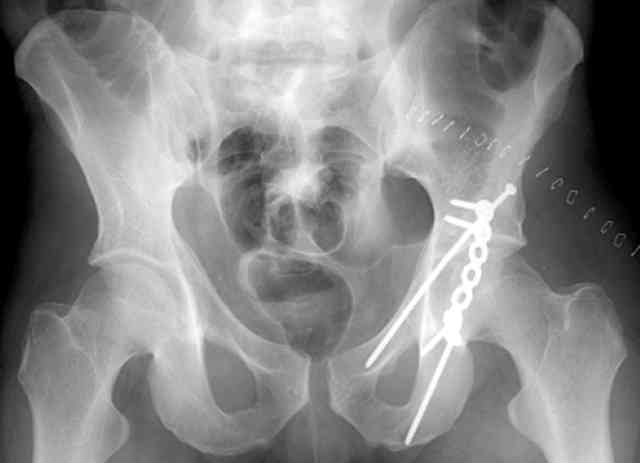

Routine Fixation

AC Screw

PC Neutr Plate

Others

The unstable caudal segment is secured by the lower 2 plate screws and the AC medullary screw... always assure that your fixation is sufficient to defeat the instability... part of your prop plan... but assure it before you close... it¹s your last chance... you shouldn't have to be pushing on the hip in contorted ways to determine your fixation stability...you can if that makes you 'comfortable'.